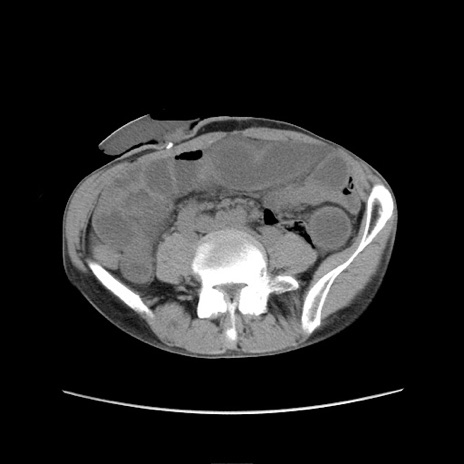

症例11(横断像)

【症例】 60歳代男性

【主訴】 下腹部痛

【現病歴】 本日夜中より下腹部痛の症状認め、受診。

【既往歴】 膀胱癌(膀胱全摘+尿管皮膚瘻術) 、胃癌術後

【身体所見】 BT 35.3℃、PR 58/min、BP 136/98mHg、腹部平坦、軟、腸蠕動音±、ストマ留置あり、左上腹部~正中部に圧痛あり、反跳痛なし。

【データ】WBC 5100、CRP0.01